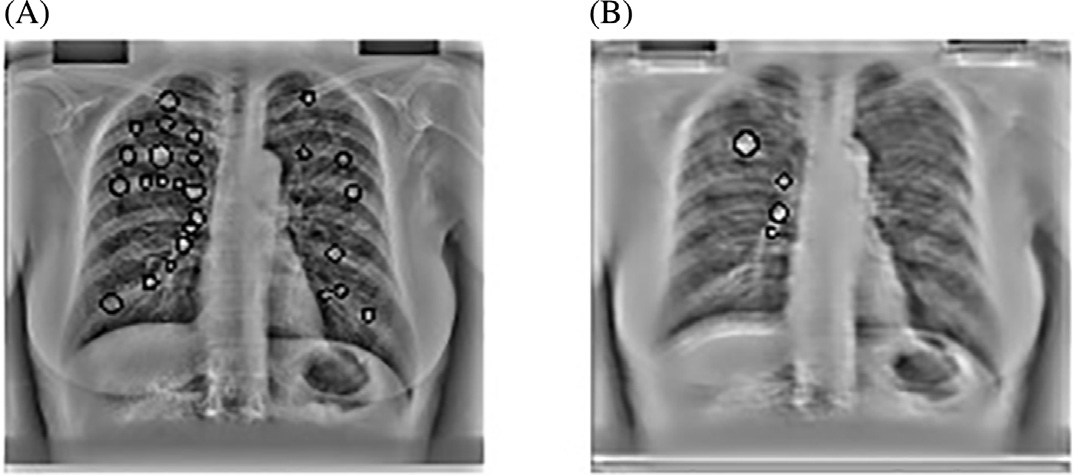

使用主成分分析滤波器进行肋骨抑制的结果如图14.2B所示。采用标准的高斯检测器高斯拉普拉斯掩模(LOG)来寻找可能存在结节的峰值区域。在原始胸部X光图像中应用该掩模导致了大量的假阳性,如图14.2A 所示,其中许多假阳性出现在肋骨上。

然而,在使用主成分分析滤波操作进行肋骨抑制后,该掩模除了检测到真正的结节外,仅产生了极少量的假阳性。人们认为,假阳性数量的减少主要归功于对肋骨的有效抑制。

之前讨论的PCA滤波技术在完整的JSRT数据库上得以实现。生成的肋骨抑制图像作为多尺度斑点检测步骤的输入。首先使用多尺度斑点检测器获取X光图像中结节的尺寸和位置。该检测器的尺度范围覆盖 σ = 1–16像素,采用九个指数间距。随后,在建立尺度空间表示后,对斑点检测器的输出应用阈值以确定极值。这些阈值的设定考虑了图像中像素值的均值和标准差。在此阶段应用的阈值应允许最大检测,以确保所有真阳性结节均被检出,因为在本阶段遗漏的任何结节在后续阶段都无法恢复。结节的尺寸可通过其被检测到的尺度进行估计。

采用PCA滤波作为预处理步骤的CAD方案输出(图14.19)。PCA滤波抑制了肋骨,从而消除了发生在肋骨上的假阳性。PCA滤波还增强了被肋骨遮挡的结节。

我们的最终第四种策略是将主成分分析滤波后的肋骨抑制图像作为计算机辅助诊断系统的输入。图14.20中可明显看到肋骨抑制的效果。采用主成分分析滤波后,每幅图像保留的候选结节平均数量降至三个。在肋骨边缘会检测到大量假阳性,而当输入为肋骨抑制图像时,这些假阳性被有效去除。此外,主成分分析滤波还提高了计算机辅助诊断系统的敏感性,因为被肋骨遮挡的癌结节变得更加显著。